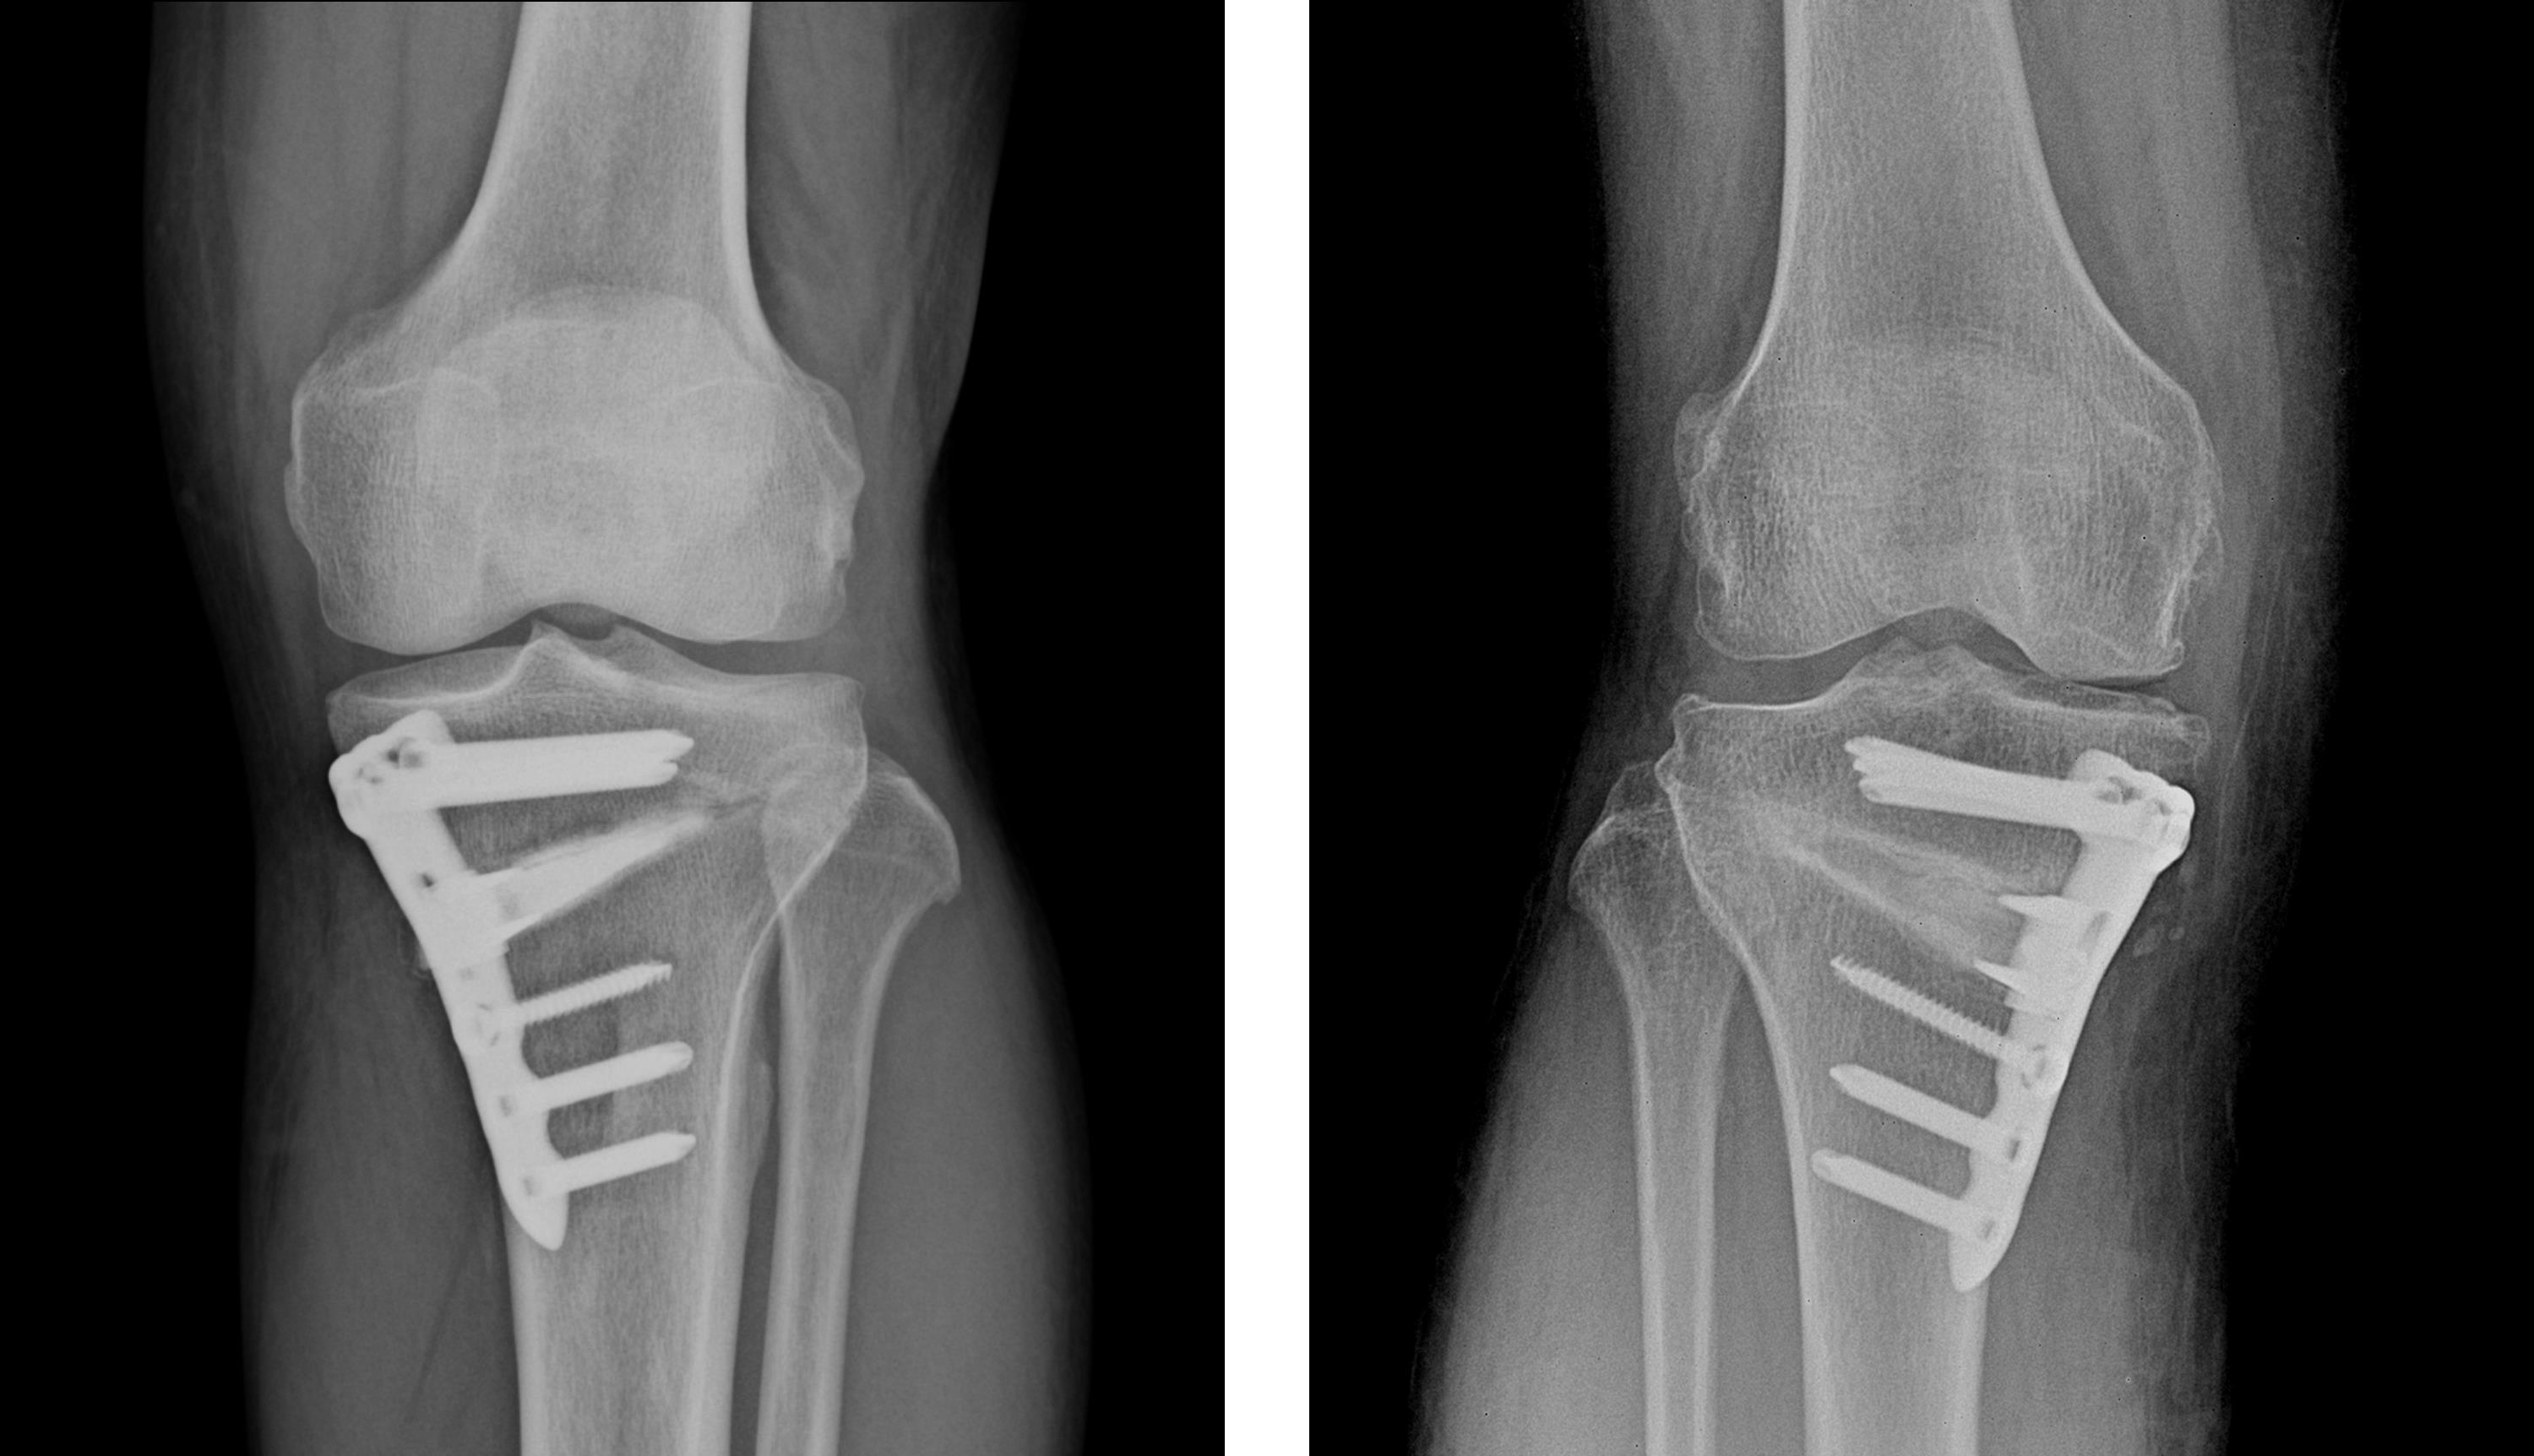

관절 연골 손상이 심한 경우 인공관절수술, 관절내시경수술, 연골판재생술, 절골술, 줄기세포치료술 등의 수술적 치료를 시행합니다.

흰다리교정수술(절골술)